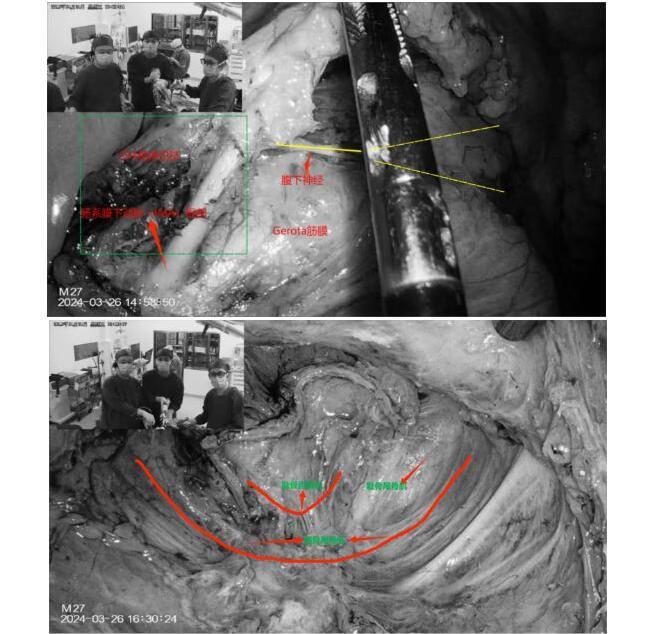

陈洪生教授凭借精湛的手术技巧和耐心细致的操作,在团队宝赛吉日呼主治医师、王中瑞住院医师的配合下,顺利通过腹腔镜完全经腹入路,自肠系膜下动脉左侧Toldt’s间隙-直肠后间隙-肛提肌上间隙,一直将直肠游离至直肠系膜终点,游离至肛提肌平面、括约肌间沟,将肿瘤提拉出肛提肌裂孔,从而获得了充足的下切缘,在保证肿瘤根治的基础上,顺利保住了肛门,同时保留了腹下神经和盆丛神经,最大程度保证术后肛门功能和排尿功能的恢复。手术层面十分清晰,观察肠管的血运良好,吻合确切。考虑到高龄患者日后再次进行手术和麻醉的风险,并没有进行保护性造口,而是留置了肛门减压管。在围手术期个体化、精细化管理下,术后第二日正常饮水,术后第五日开始进流食,在正常排便后逐步撤离了肛管和盆腔引流管,患者术后恢复良好,没有出现吻合口瘘,肛门的功能也保留完好。

81岁的周老(化名)因间断便血,肠镜检查发现直肠恶性肿瘤,肠镜及直肠核磁评估肿瘤距肛缘5cm,肿瘤的位置同样很低,患者及家属为求保肛手术治疗,慕名找到陈洪生教授。通过细致的术前评估和术前准备,在克服了男性骨盆狭窄等不利条件下,经过艰苦的努力,陈洪生教授团队再次成功实施了“腹腔镜完全经腹入路直肠括约肌间切除术(ISR)”,既切除了直肠的恶性肿瘤,又极限地保留了肛门和肛门的功能。